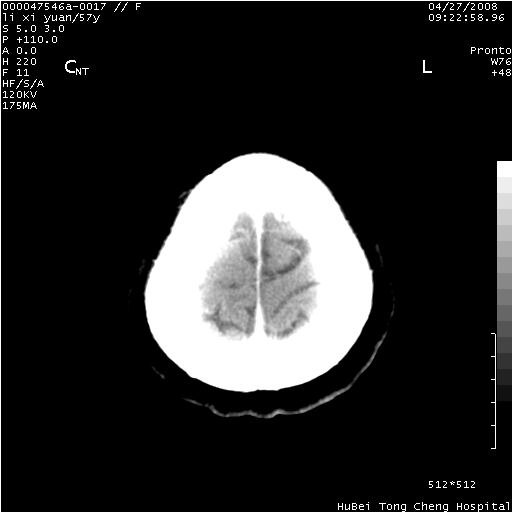

以下是引用余辉在2008-4-27 14:02:00的发言:[br]病灶位于中央沟前方?位于额叶?高密度灶,灶周水肿不明显,病灶似沿脑沟走行,强化明显,局部层面呈现环状强化,考虑1脑表面血管性疾病,如血管瘤,血管扩张,灶内血栓形成,其次考虑肿瘤如脑膜瘤、转移瘤,胶母等

以下是引用形影不离在2008-4-27 14:13:00的发言:[br]考虑胶质瘤可能性大,不排除慢性炎性肉芽肿。建议mri检查。